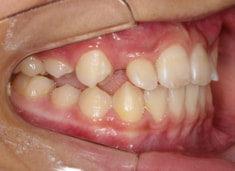

骨年齢は実年齢よりも低めなので、今後下顎の旺盛な成長が見込まれます。

検査時のレントゲン分析では、上下顎の関係は、上顎の劣成長があり下顎前突傾向という値がでておりましたが、前歯ジャンプ後はフェイスマスクの効果もあり、上下顎の関係は正常化しています。

上顎が若干優位になっていますので、今後の下顎の成長のための貯金になっているくらいです。